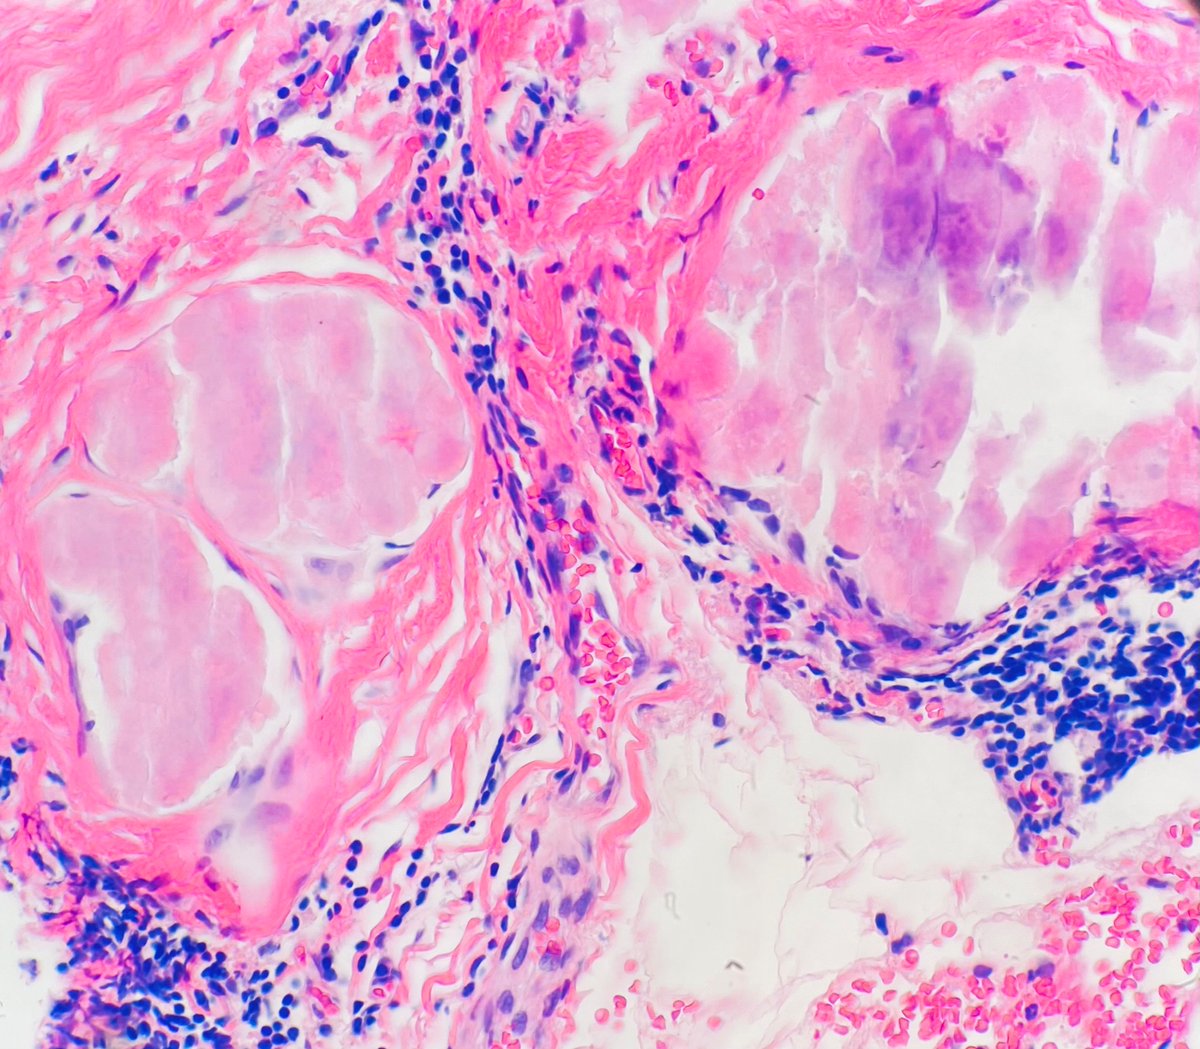

Primary localized amyloid of the breast #breastpath #PathTwitter #MedTwitter #pathology 🍏Detected on screening mammography as clusters of calcifications 🍏 25% do not develop a hematologic disorder or systemic amyloidosis 🍏Apple-green on polarized light